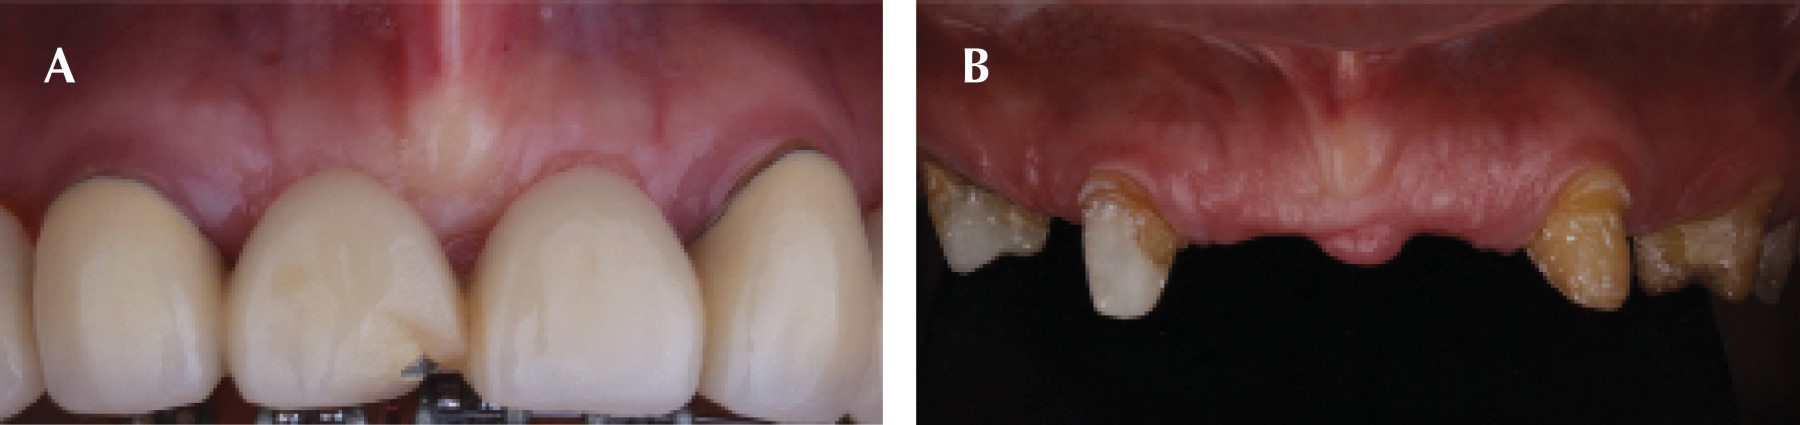

Figure 1

Figure 2

Figure 3

Figure 4

Figure 5